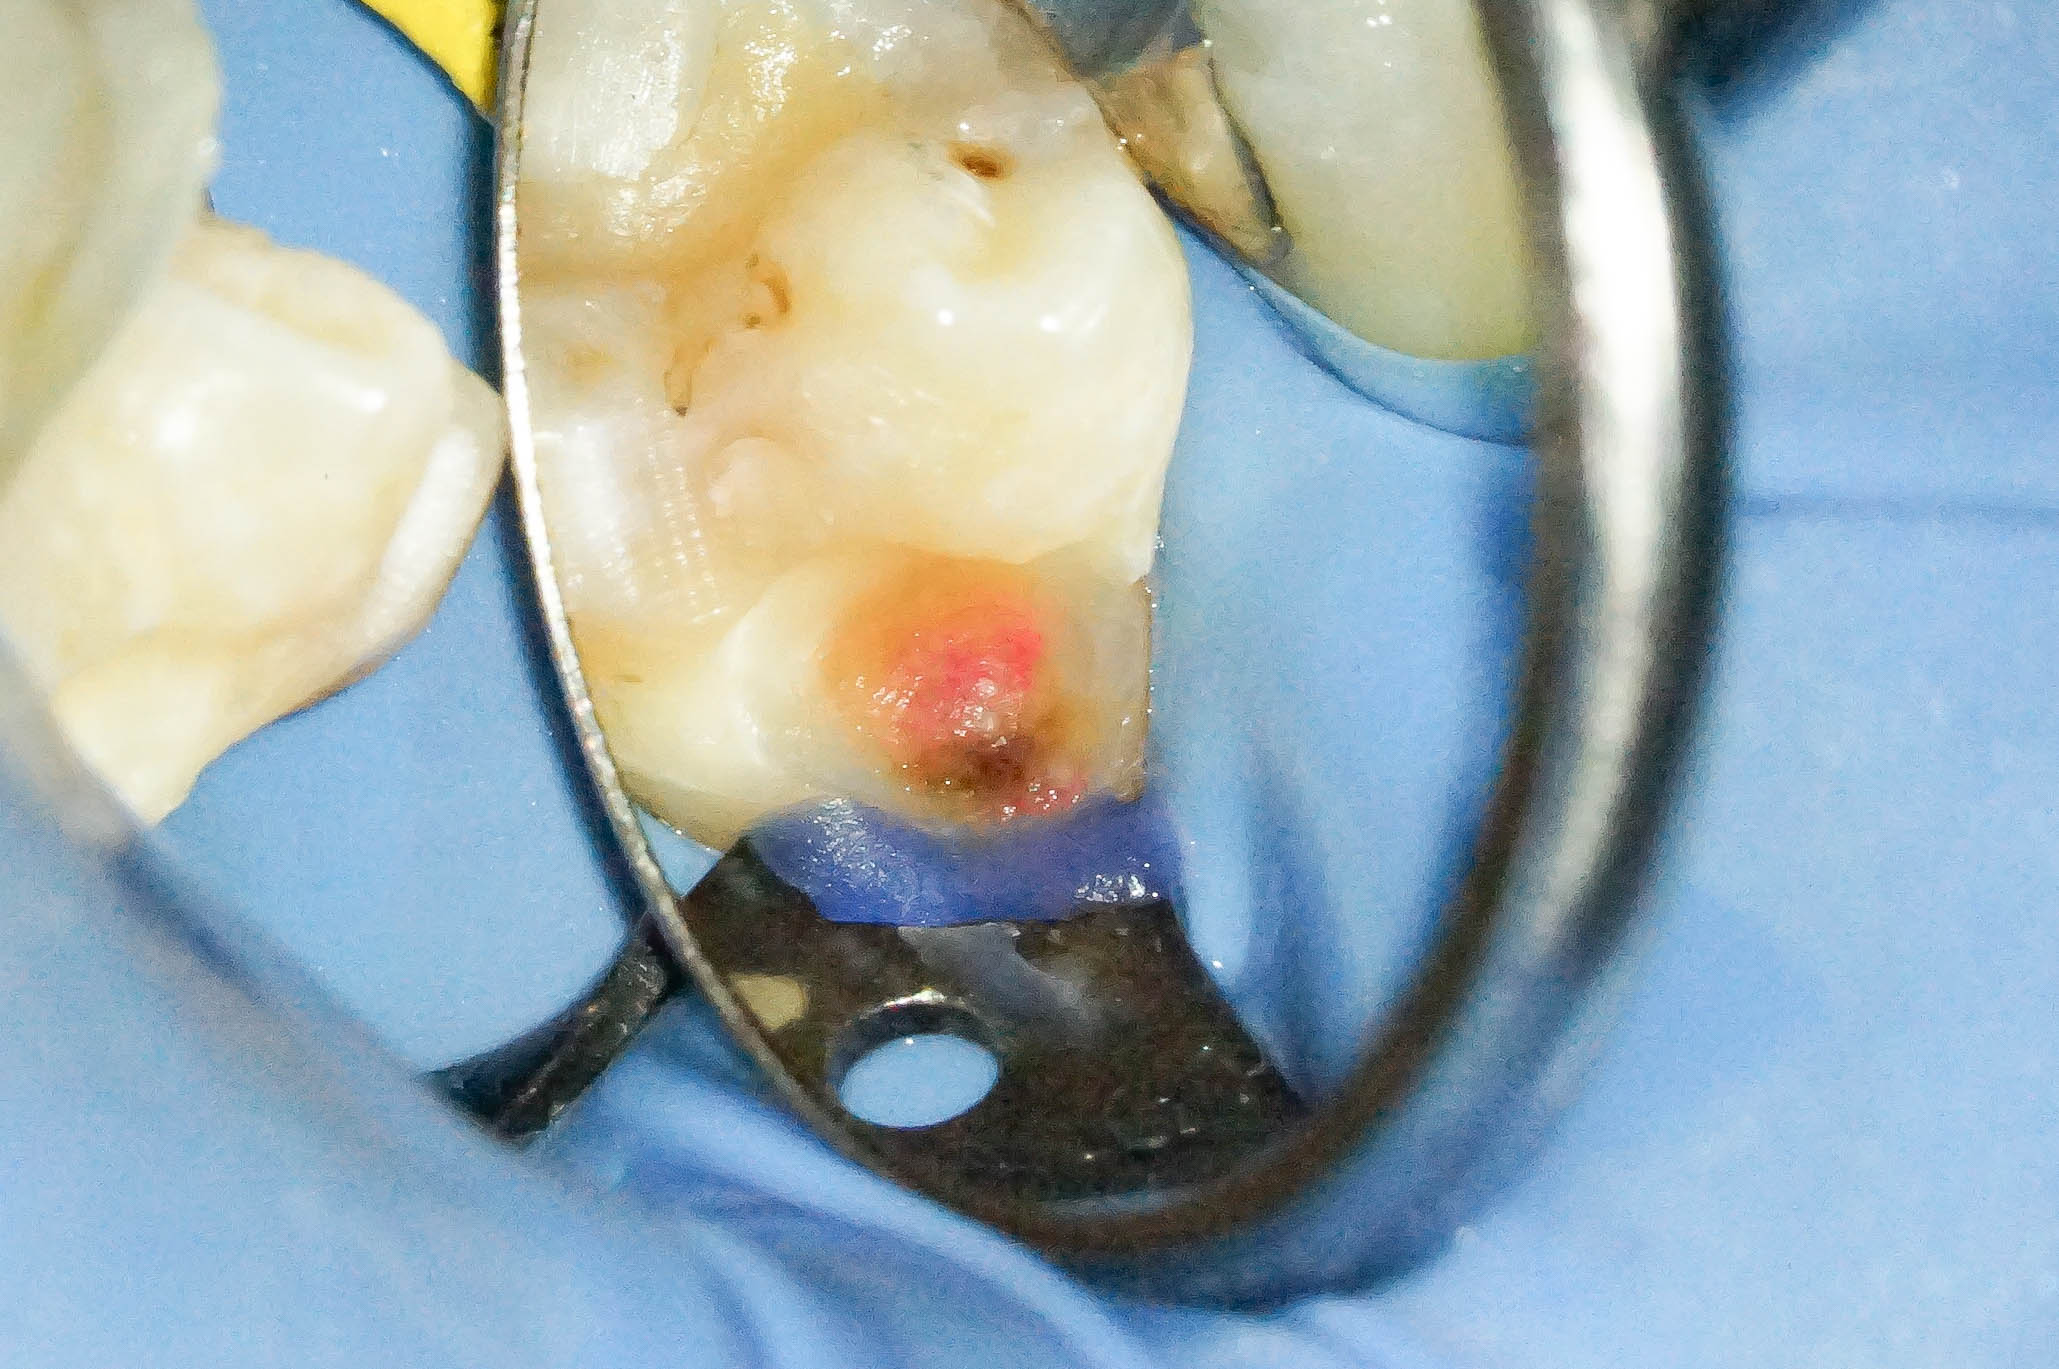

歯肉縁下ダイレクトボンディングを行った症例治療方法02

拡大して見てみると歯と歯肉の境目に齲蝕を認めます。

いわゆる普通の、保険治療でよく見かけるコンポジットレジンのその後 ですね。

治療直後はなにもトラブルが起きていませんが、数年後にトラブルが起き始める典型的な例です。

歯周外科を行うことでウ蝕部分をしっかりと明示できるので、ウ蝕の取り残しをなくすことができます。

そして難易度は高いですが、その部位にラバーダムを設置します。

ラバーダムがなければ処置部位は血まみれ、唾液まみれで繊細な治療ができません。

古いコンポジットレジンを除去したところ、やはり内部でウ蝕が広がっていました。

確実な視野の確保、そして清潔な領域を守りつつ作業ができるので、ラバーダムの効果は絶大です。

ウ蝕検知液を使用して徹底的に軟化象牙質を除去していきます。

ウ蝕を取りきったところ、露髄(神経が露出)を認めました。

ちなみにこの時点で唾液が一滴でも歯髄に付着すると、歯髄温存の可能性が著しく低下します。MTAセメントで歯髄温存療法を行う際にはラバーダムは必須です。

断髄せず保存が望めそうだったため、露髄部にMTAセメントを適用しました。